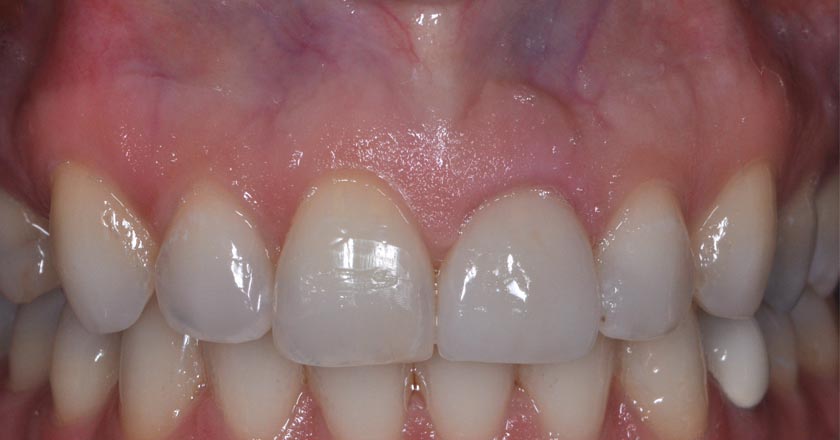

Gummy Smile - Before And After

Gummy smile correction – before treatment 2

Gummy smile correction – after treatment 2